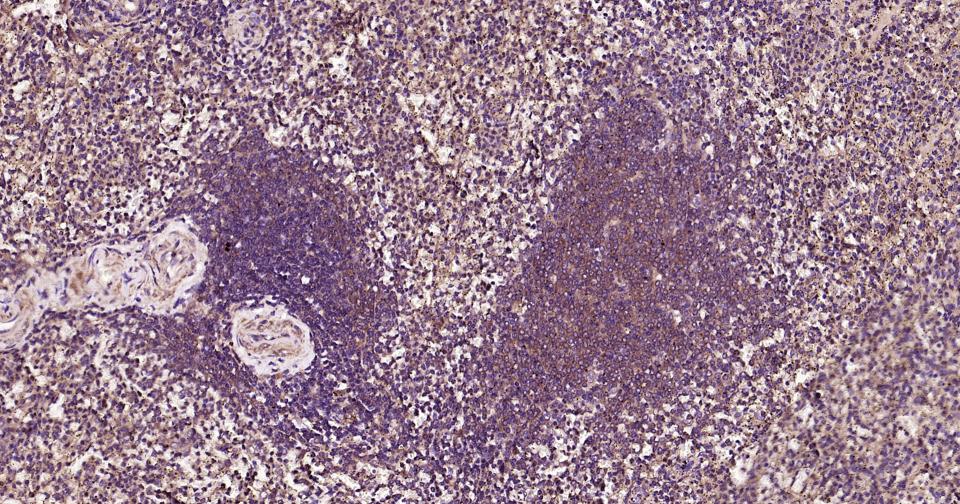

Paraformaldehyde-fixed, paraffin embedded Human Spleen; Antigen retrieval by boiling in sodium citrate buffer (pH6.0) for 15 min; Antibody incubation with MyD88 Monoclonal Antibody, Unconjugated(bsm-61269R) at 1:200 overnight at 4°C, followed by conjugation to the bs-0295G-HRP and DAB (C-0010) staining.